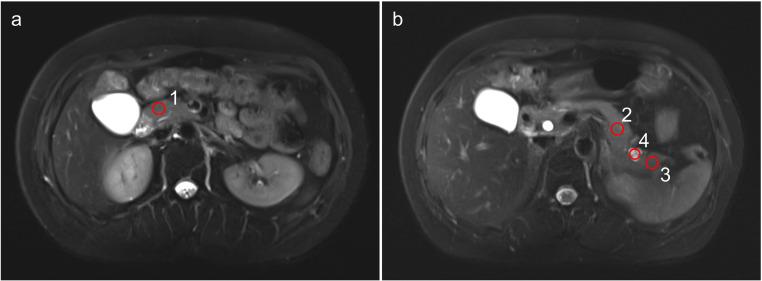

The objective of this study was to evaluate the clinical feasibility of deep learning reconstruction-accelerated thin-slice single-breath-hold half-Fourier single-shot turbo spin echo imaging (HASTE) for detecting pancreatic lesions, in comparison with two conventional T2-weighted imaging sequences: compressed-sensing HASTE (HASTE) and BLADE.

From March 2022 to January 2023, a total of 63 patients with suspected pancreatic-related disease underwent the HASTE, HASTE, and BLADE sequences were enrolled in this retrospectively study. The acquisition time, the pancreatic lesion conspicuity (LC), respiratory motion artifact (RMA), main pancreatic duct conspicuity (MPDC), overall image quality (OIQ), signal-to-noise ratio (SNR), and contrast-noise-ratio (CNR) of the pancreatic lesions were compared among the three sequences by two readers.

The acquisition time of both HASTE and HASTE was 16 s, which was significantly shorter than that of 102 s for BLADE. In terms of qualitative parameters, Reader 1 and Reader 2 assigned significantly higher scores to the LC, RMA, MPDC, and OIQ for HASTE compared to HASTE and BLADE sequences; As for the quantitative parameters, the SNR values of the pancreatic head, body, tail, and lesions, the CNR of the pancreatic lesion measured by the two readers were also significantly higher for HASTE than for HASTE and BLADE sequences.

Compared to conventional T2WI sequences (HASTE and BLADE), deep-learning reconstructed HASTE enables thin slice and single-breath-hold acquisition with clinical acceptable image quality for detection of pancreatic lesions.